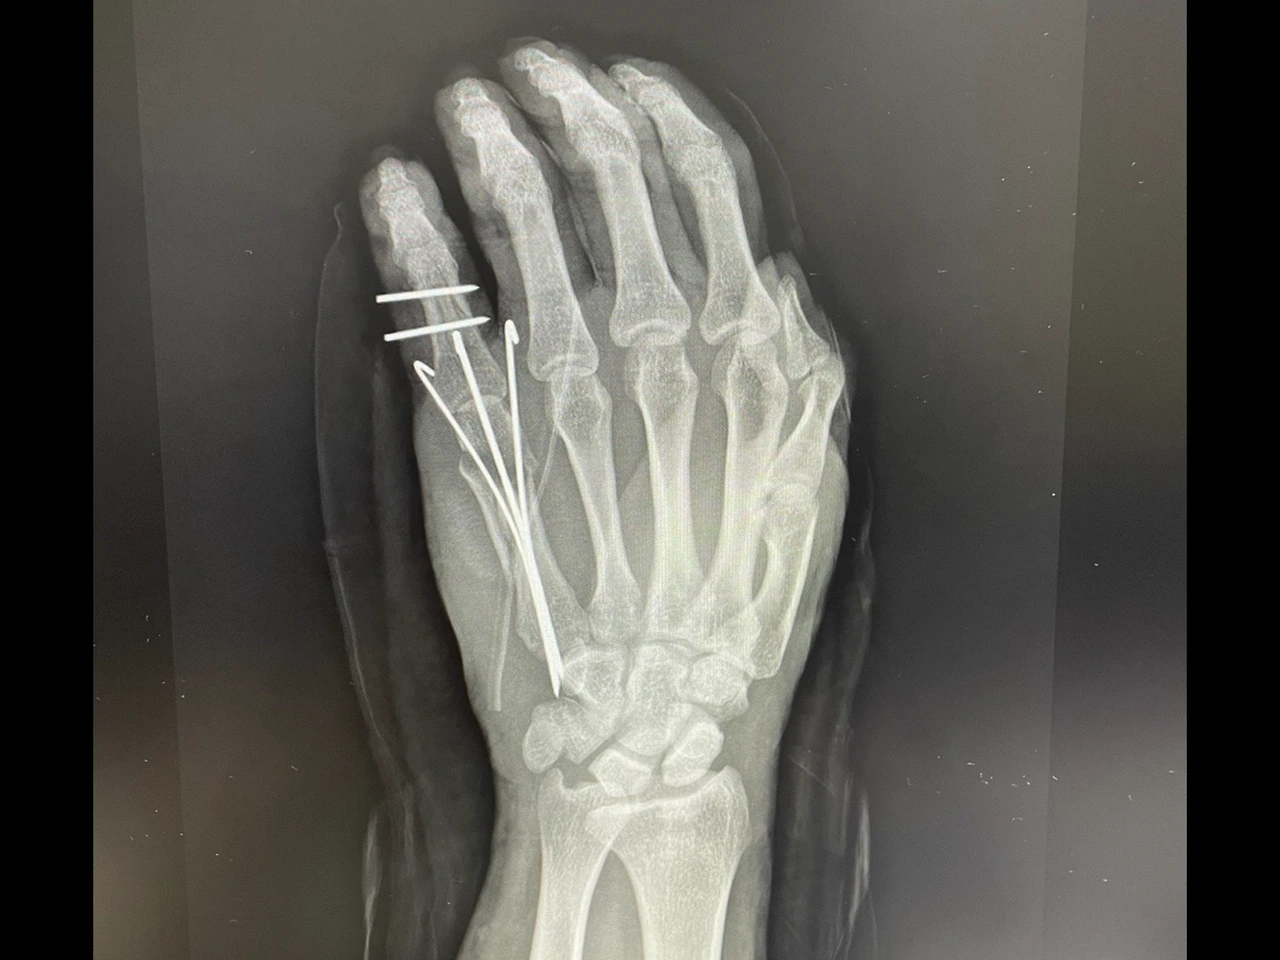

진단명은 소지 개방 골절 및 분쇄골절이었다. 뼈가 심하게 조각나서 완벽하게 붙일 수 없었고 완벽하게 붙이면 손을 움직일 수 있는 확률이 현저히 떨어진다고 하였다.

밑에 사진은 심신미약자는 보지 않는 걸 권고한다.